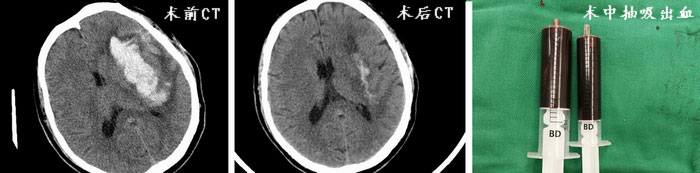

10月12日,我院神经外科通过绿色通道收治了3名危重脑出血患者,入院时患者均有严重的意识及肢体功能障碍。神经外科团队针对患者病情展开讨论,根据患者症状体征及影像学检查,手术指征明确,决定采取颅内血肿穿刺引流。与以往不同的是,术中将使用机器人精准确定病灶穿刺靶点、合理规划并选择路径,从而达到最佳的引流效果。3例不同病变部位颅内血肿在机器人辅助引导下顺利完成穿刺,术后复查头部CT提示颅内出血引流效果满意,三位患者意识及肢体功能得到明显改善,目前正在康复治疗中。

对比图.jpg